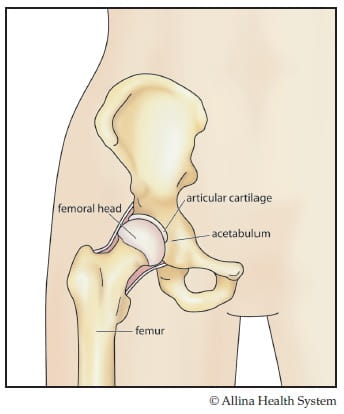

Normal hip-color

In the normal hip, the ball and socket are covered with a smooth layer of tissue (cartilage).

The hip is a ball and socket joint. The ball is formed by the head of the femur (the thigh bone). The socket is part of the pelvis called the acetabulum.

In a normal hip, the ball and socket are covered with a smooth layer of tissue called cartilage. The cartilage allows the ball to glide easily inside the socket and provides a cushion to your hip joint.

Muscle and ligaments hold your hip joint in place. When the surrounding muscles support your weight and the joint moves smoothly, you can walk without pain.